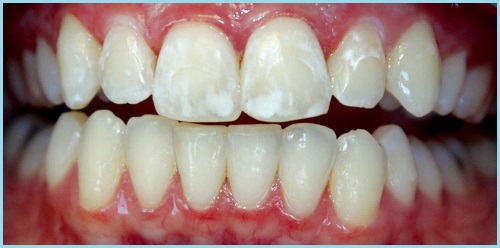

1. Стадия пятна.При осмотре на поверхности зуба обнаруживается белое или темное пятнышко. На этой стадии человек обычно не испытывает никаких неприятных ощущений. Часто такие пятна встречаются после снятие брекетов, когда пациент должным образом не смог правильно чистить зубы.